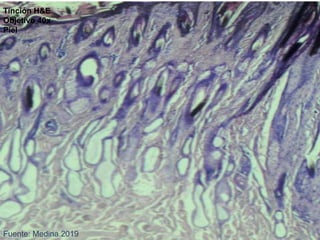

MICROSCÓPICOS

Fuente: Medina.2019

Tinción H&E

Objetivo 40x

Piel